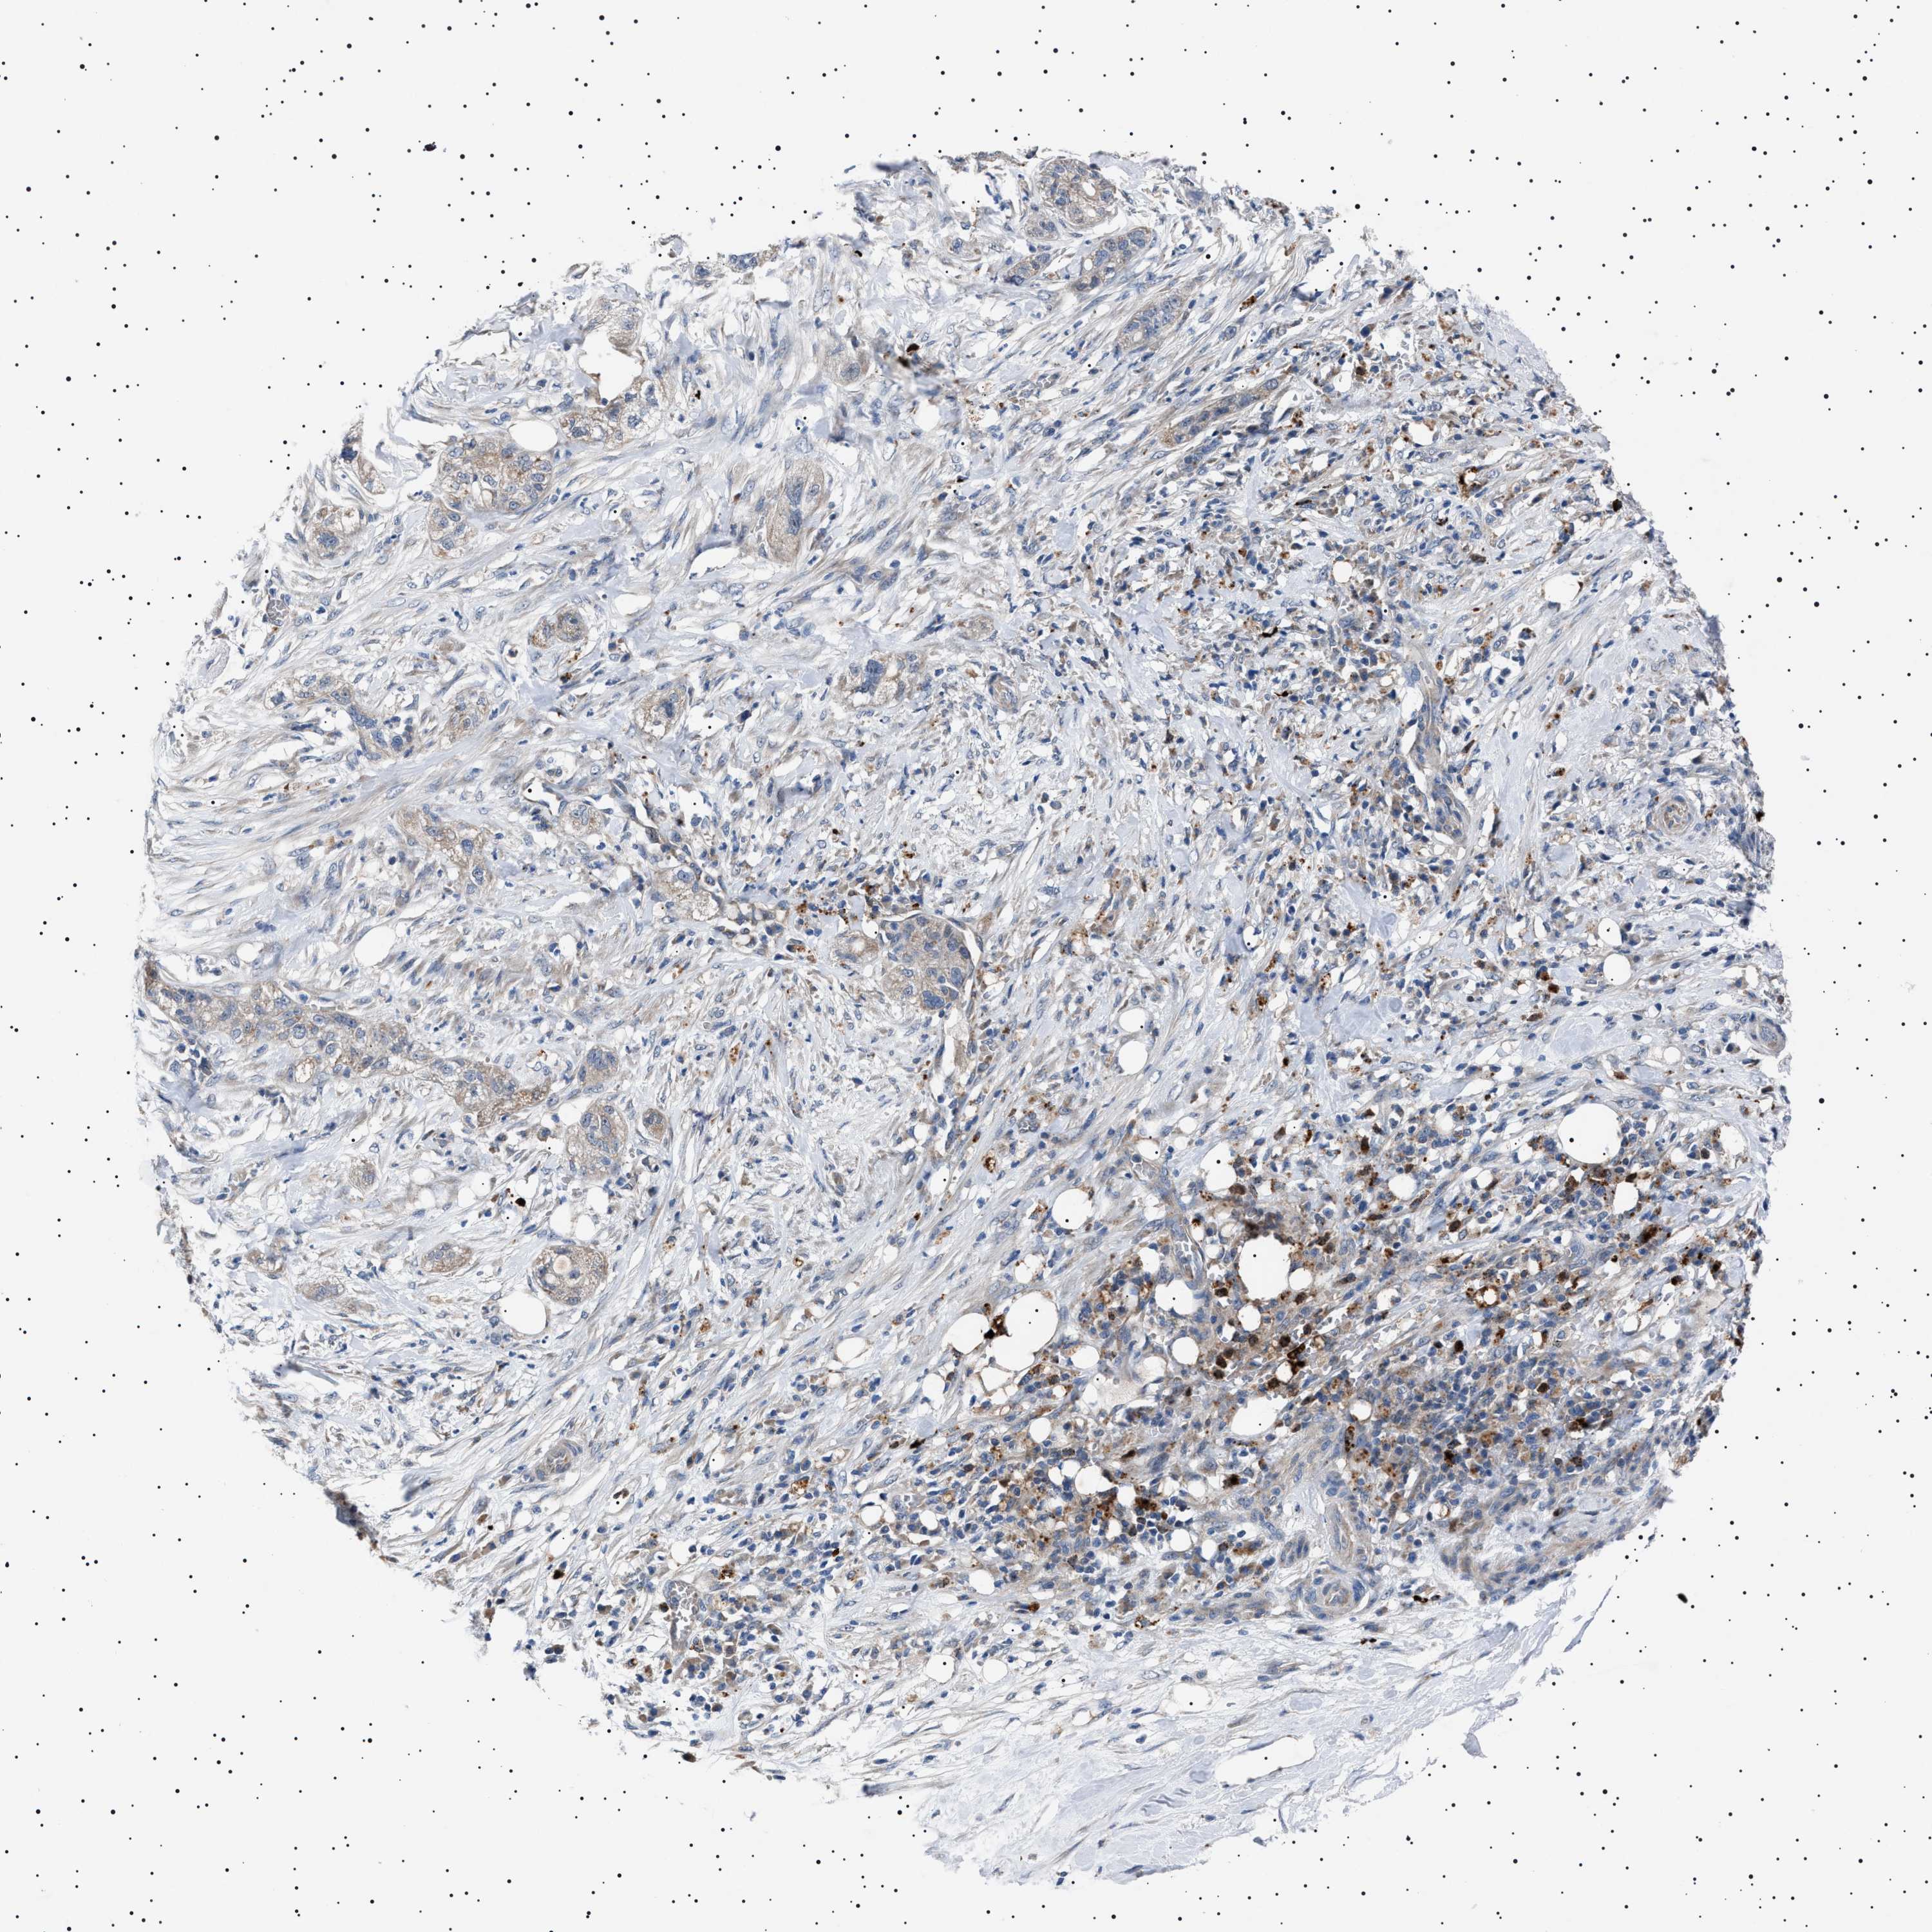

PANCREATIC CANCER - Protein expressioni

A mouse-over function shows sample information and annotation data. Click on an image to view it in a full screen mode. Samples can be filtered based on level of antibody staining by selecting one or several of the following categories: high, medium, low and not detected. The assay and annotation is described here.

Note that samples used for immunohistochemistry by the Human Protein Atlas do not correspond to samples in the TCGA dataset.

Antibody stainingi

Antibody staining in the annotated cell types in the current human tissue is reported as not detected, low, medium, or high, based on conventional immunohistochemistry profiling in selected tissues. This score is based on the combination of the staining intensity and fraction of stained cells.

Each image is clickable and will lead to virtual microscopy that enables deeper exploration of all samples and also displays staining intensity scores, fraction scores and subcellular localization as well as patient and tissue information for each sample.

Antibody HPA021223

Staining

High

Medium

Low

Not detected

Intensity

Strong

Moderate

Weak

Negative

Quantity

>75%

75%-25%

<25%

None

Location

Nuclear

Cytoplasmic/membranous

Cytoplasmic/membranous,nuclear

Adenocarcinoma, NOS